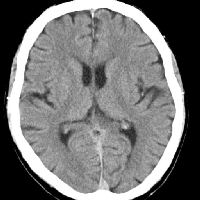

Und hier meine CT Aufnahmen...

Vielleicht sind hier ja ein paar Spezialisten die mir mehr sagen können.

Ich finde ich hab auch so wenig furchen, zB wie hier beschrieben...

Außerdem fanden sich in seinen Scheitellappen weniger Furchen als in Vergleichshirnen.http://www.wissenschaft-online.de/artikel/992155

Und was mir auch auffällt das ich an den Seiten diese furchen nicht habe....

Ein Team um Sandra Witelson von der kanadischen McMasters-Universität in Hamilton zeigte, dass bei Einstein eine seitliche Region der Großhirnrinde stark entwickelt war. Dort ist das mathematische Denken, aber auch die Vorstellung von Bewegungen lokalisiert. Bei Einstein fehlte zudem eine sonst übliche Furche in der Gehirnregion, was auf mehr Nervenverbindungen hindeuten könnte.http://www.focus.de/wissen/diverses/einstein_aid_90435.html

Wär schön wenn mir jemand mehr sagen könnte.